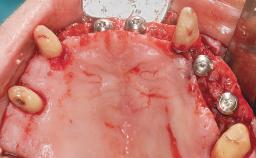

Immediate Loading of Six Implants in the Maxilla and Final Restoration with a Full-Arch CAD/CAM Zirconia FDP

A 63-year-old male patient was referred for a consultation and treatment of partial edentulism in the maxilla. The patient presented with residual anterior teeth and declined a partial removable prosthesis. He reported that the maxillary posterior teeth had been extracted due to mobility and periodontal disease two months before the consultation. The patient’s chief complaint was that his residual maxillary teeth were mobile and that he was unable to chew. The patient’s desire was a stable and comfortable fixed maxillary rehabilitation. The patient was a light smoker (fewer than 10 cigarettes/ day), and his medical history was without significant findings. He was not on any regular medication at the time of consultation. The extraoral examination revealed a normal physiognomy with a correct distribution of the facial thirds. The patient presented a low lip line, and the transition line between teeth and soft tissues was not exposed during a forced smile.

# of Implants 6

Bone Augmentation Horizontal|Simultaneous

Defining Characteristics Fully edentulous upper jaw to be rehabilitated with four or more implants

Modality 6+ implants with immediate loading

Bone Volume Horizontally and vertically sufficient